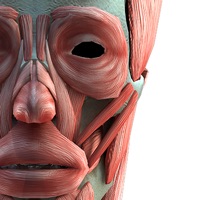

3D人体模型提供全三维数字人体模型,超过4000多个人体解剖结构,完整全面的解剖学数据,涵盖人体各个解剖系统,如神经,运动,呼吸,心血管,泌尿等系统,并配有文字注释,触发点等信息。 此APP功能强大,是广受欢迎的医学软件之一。其主要包括12个系统: 循环系统,消化系统,内分泌系统,皮肤系统,淋巴系统,肌肉系统,神经系统,生殖系统,泌尿系统,呼吸系统,骨骼系统和骨连接系统。 主要特点: 真正的3D特效,能360度任意角度查看,分层查看,进行相关组织或解剖结构隐藏,显示,完全再现人体解剖全过程。 能无限级的放大和缩小,远距离观察全景,近距离观察细节。 全面的功能: 具有分享,收藏,画笔,截图等功能。 1.0版上线 * 所有企业logo、商品标识、期刊封面版权皆为对应公司或期刊所有。本软件作为介绍使用,应视作合理引用。